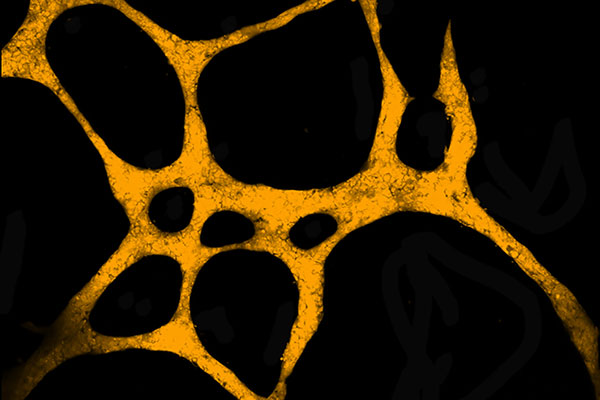

The Tumour Network

Kay Myo Min

School of Pharmacy and Medical Sciences

This image depicts the ability of cancer cells to form blood vessel-like structures so that they can gain access to the blood supply, a process known as "vasculogenic mimicry". This phenomenon is observed in highly aggressive forms of solid tumours and is correlated with poor patient survival outcomes.